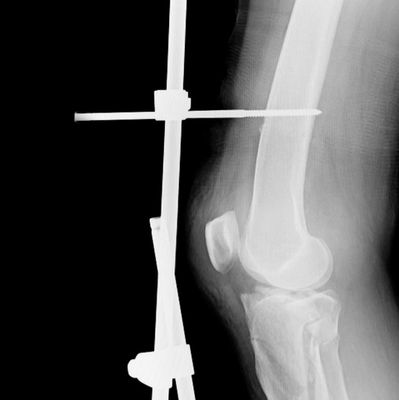

Te invitamos a nuestra 3era edición de este diplomado el cual será administrado en conjunto al Instituto CSF, siendo esta una oportunidad de profundizar y subespecializar al personal quirúrgico de enfermería en el área de traumatología y osteosíntesis, contemplando como una continuidad a nuestro diplomado de instrumentación quirúrgica en cirugía general del cual tenemos más de 45 ediciones, el cual será impartido de la mano de la Dra. Katiuska La Chica, enfermera con más de 30 años en el área quirúrgica, dándole la oportunidad a los inscritos de poder manipular instrumental real utilizado en quirófanos los cuales utilizarás en situaciones simuladas para realizar prácticas supervisadas. Adicional, al finalizar la formación teórica, tendrá un ciclo de pasantías garantizadas por la coordinación del programa en el área quirúrgica de alguno de los centros asistenciales aliados.

No pierdas la oportunidad de formarte en una de las áreas más cotizadas y lucrativas de la enfermería en los últimos tiempos, tanto en Venezuela como en Estados Unidos y Europa.

Al concluir el programa se emitirá la credencial correspondiente al Diplomado en enfermería quirúrgica en traumatología y osteosíntesis avalado por el Instituto universitario de Tecnología Rufino Blanco Fombona y el Instituto CSF, el cual se puede apostillar para uso en el extranjero.